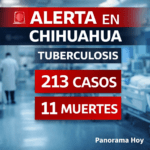

📊 Panorama en Chihuahua

De acuerdo con datos del sector salud:

- Actualmente hay 14 personas diagnosticadas en atención inicial

- En 2025 se registraron 335 defunciones en el estado

- En lo que va de 2026, se han reportado 43 muertes por esta causa

- El año pasado se atendieron 102 pacientes en instituciones de salud

Estas cifras reflejan la magnitud del problema y la importancia de la prevención.